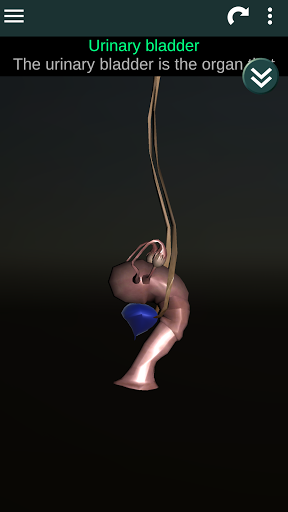

Internal Organs in 3D Anatomy لـ Vodafone Smart N9 Lite

(الأجهزة الداخلية في)

Internal Organs 3D Anatomy 3.4

يمكنك هنا تنزيل ملف حزمة تطبيق أندرويد "Internal Organs 3D Anatomy" الخاصة بجهازVodafone Smart N9 Lite مجانًا، نسخة ملف حزمة تطبيق أندرويد - 3.4 للتحميل على Vodafone Smart N9 Lite اضغط ببساطة على هذا الزر. إنه سهل وآمن. نحن نقدم فقط ملفات حزمة تطبيق أندرويد الأصلية. إذا انتهكت أية مواد موجودة في الموقع حقوقك قم بإبلاغنا من خلال